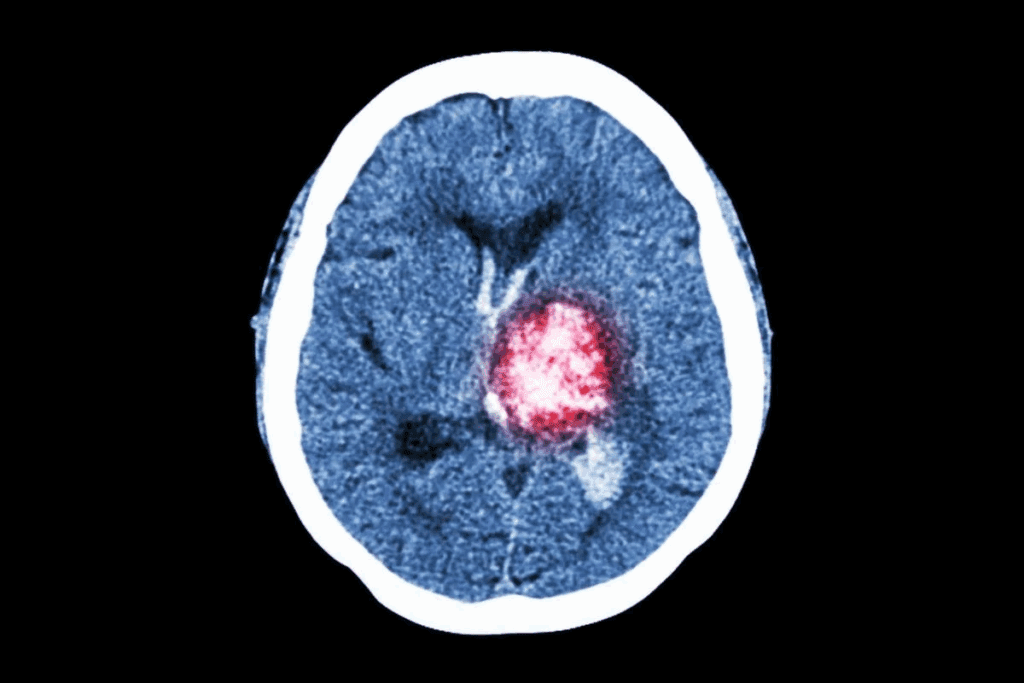

Neuroimaging Techniques (MRI, CT, PET)

Neuroimaging is a big deal in finding brain tumors. MRI, CT scans, and PET scans are at the top of the list for seeing tumors clearly.

- CT scans: Fast and useful in emergencies, they show tumors and other issues like bleeding or calcification.